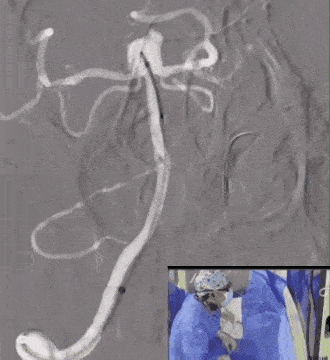

解脱后再次造影,多角度提示动脉瘤瘤腔内有明显造影剂滞留,基底动脉及其分支通畅。

术后麻醉良好,手术顺利,患者生命体征平稳。